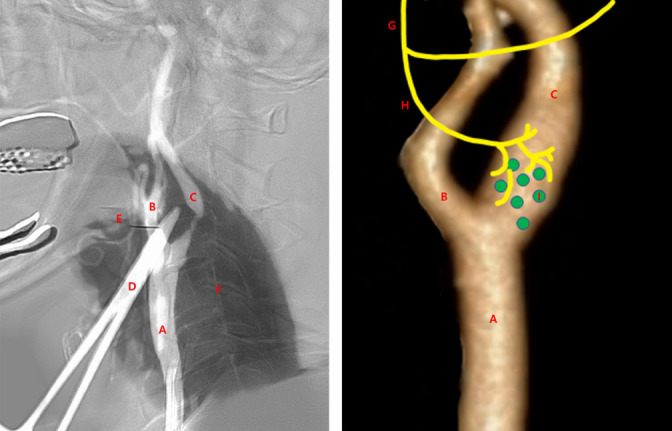

Results: Among patients who received PPLIs, the mean degree of stenosis was 80.5% (95% confidence interval [CI]: ±10.74, 51-98%). The mean distance from the common carotid artery bifurcation to the most stenotic lesion (CSD) was 8.3 mm (95% CI: ±0.97, 6.3-10.2 mm); the mean angle between the internal carotid artery and common carotid artery (CCA) trunk (IAG) was 65.6° (95% CI: ±2.39, 61-70°). Among patients who did not receive PPLIs, the mean degree of stenosis was 84.0% (95% CI: ±8.96, 70-99%). The mean CSD was 5.9 mm (95% CI: ±1.83, 1.9-9.9 mm); the mean IAG was 60.4° (95% CI: ±4.41, 51-70°). The procedure time was longer in the PPLI group than in the no PPLI group (28.19 [n=39] vs. 18.88 [n=12] days) (P=0.057); the length of intensive care unit stay was shorter in the PPLI group (20.01 [n=36] vs. 28.10 [n=5] days) (P=0.132).

Conclusions: Targeted PPLI administration to the carotid bulb decreased aberrant heart rates and blood pressure changes induced by carotid stent deployment and balloon inflation. As CBR sensitivity increases with decreasing distance to the stenotic lesion from the CCA bifurcation, PPLIs may help stabilize patients during procedures for stenotic lesions closer to the CCA.